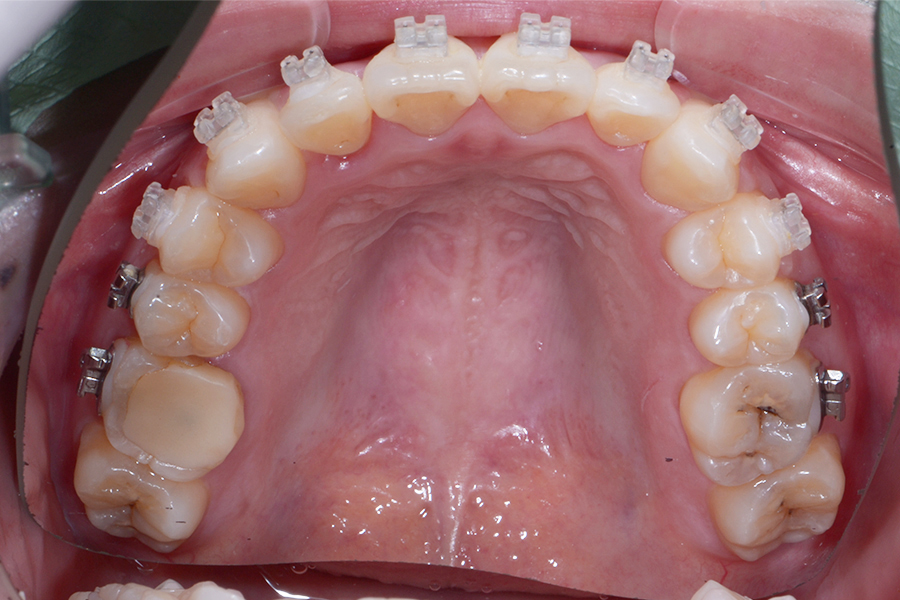

• 治療前

治療内容 上顎ラビアル矯正(表側矯正)